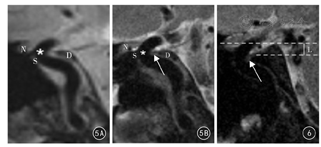

矢状位3D-SPACE-T2WI、HR-DIR-T2WI显示同层面DDR图像(图5):两种扫描序列均能显示出DDR前后缘,视神经、视柱的硬膜延续与颈内动脉床突段间形成DDR前缘,鞍背的硬膜延续与颈内动脉床突段间形成DDR后缘。3D-SPACE-T2WI序列DDR后缘显示欠清晰,未能清晰锐利地显示出硬膜的细节(图5A)。HR-DIR-T2WI序列显示硬膜隔更为清晰锐利,显示DDR后缘形成小凹样结构(图5B及图6)。

20例(40侧)志愿者中,3D-SPACE-T2WI序列上,观察到颈动脉窝23侧,其中B型16侧、C型7侧;颈动脉窝深度1.0~7.5 mm,平均(2.07±1.31)mm。HR-DIR-T2WI序列上,观察到颈动脉窝19侧,其中B型13侧、C型6侧;颈动脉窝深度1.1~7.5 mm,平均(2.13 ±1.33)mm。结果显示,颈动脉窝区结构细小且模糊,HR-DIR-T2WI序列对于颈动脉窝的显示更为清晰,增加了分型及测量的准确性;两种序列颈动脉窝深度比较,差异无统计学意义(t=0.144, P>0.05)。

DDR向外附着于前床突,向前紧密地附着于与颈内动脉邻近的视柱。由于视柱与颈内动脉前壁之间间隙狭小,DDR前缘覆盖视柱,几乎呈融合状[7,8,9],故MRI未显示前隔时,可以视柱上缘为DDR前缘的解剖标志。解剖学研究表明,DDR并非沿着一个完全的水平面走行,而是呈外高内低、前高后低倾斜;外高内低倾斜角位平均为21.8° ,前高后低倾斜角平均为20.3° [2,7]。在本研究中,DDR在冠状位呈外高内低倾斜,倾斜角度(左侧平均值17.3°,右侧平均值17.8°)略低于既往解剖测量结果;在矢状位首次采用MRI方法测量DDR倾斜角及形态,所测DDR倾斜面方向为前高后低,与既往解剖学研究基本相同,但倾斜角度(左侧平均值14.65°,右侧平均值11.58°)低于既往解剖研究。笔者分析,DDR倾斜角度的测量有一定差异,可能是研究采用的测量方法差异所致。颈动脉窝位于DDR后内侧,是远端硬膜环末端形成的囊袋样结构,其底端含有丰富的疏松结缔组织,有时与蛛网膜下腔相沟通,容易造成蛛网膜下腔出血[1,2,5,10]。既往解剖学研究显示,颈动脉窝深度的测量结果各不相同。Oikawa等[2]测量颈动脉窝深度平均值1.6 mm(0.5~3.2 mm);而Joo等[10]解剖学研究显示,颈动脉窝深度平均值2.4 mm(1.5~5 mm)。本研究在3D-SPACE-T2WI及HR-DIR-T2WI两种序列上,矢状位后侧颈动脉窝深度平均值分别为(2.07±1.313)mm(1~7.5 mm)和(2.13 ±1.332)mm(1.10~7.5 mm)。本研究结果与文献[10]报道的解剖学研究数据存在一定差距,笔者分析,本次研究着重后侧及内侧颈动脉窝的测量,与文献报道后内侧颈动脉窝测量角度不同,故颈动脉窝的测量方法有待进一步完善。颈动脉窝内动脉瘤位于DDR的远侧,属于硬膜下动脉瘤。当颈动脉窝较深而动脉瘤又位于颈动脉窝内时,由于动脉瘤位置较低,可能位于眼动脉水平以下[11],而误诊为硬膜外动脉瘤,因此观察颈动脉窝深度有重要的临床意义。